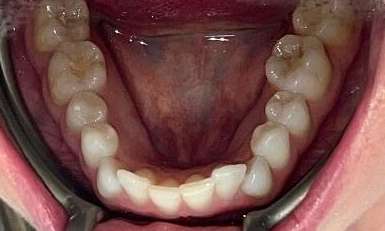

This patient presented with concerns about the damage his teeth had sustained from his bite and previous habits. His lower teeth had caused erosion and wear on the palatal surfaces and incisal edges of his upper front teeth. He was also concerned about the crowding of the lower front teeth. His primary goal was to create a more protected alignment and function of his teeth to support better oral health and longevity.

Due to a sensitive gag reflex, he first trialled nightly whitening trays for two weeks to assess whether he could tolerate aligner wear. This approach gave him the confidence ...